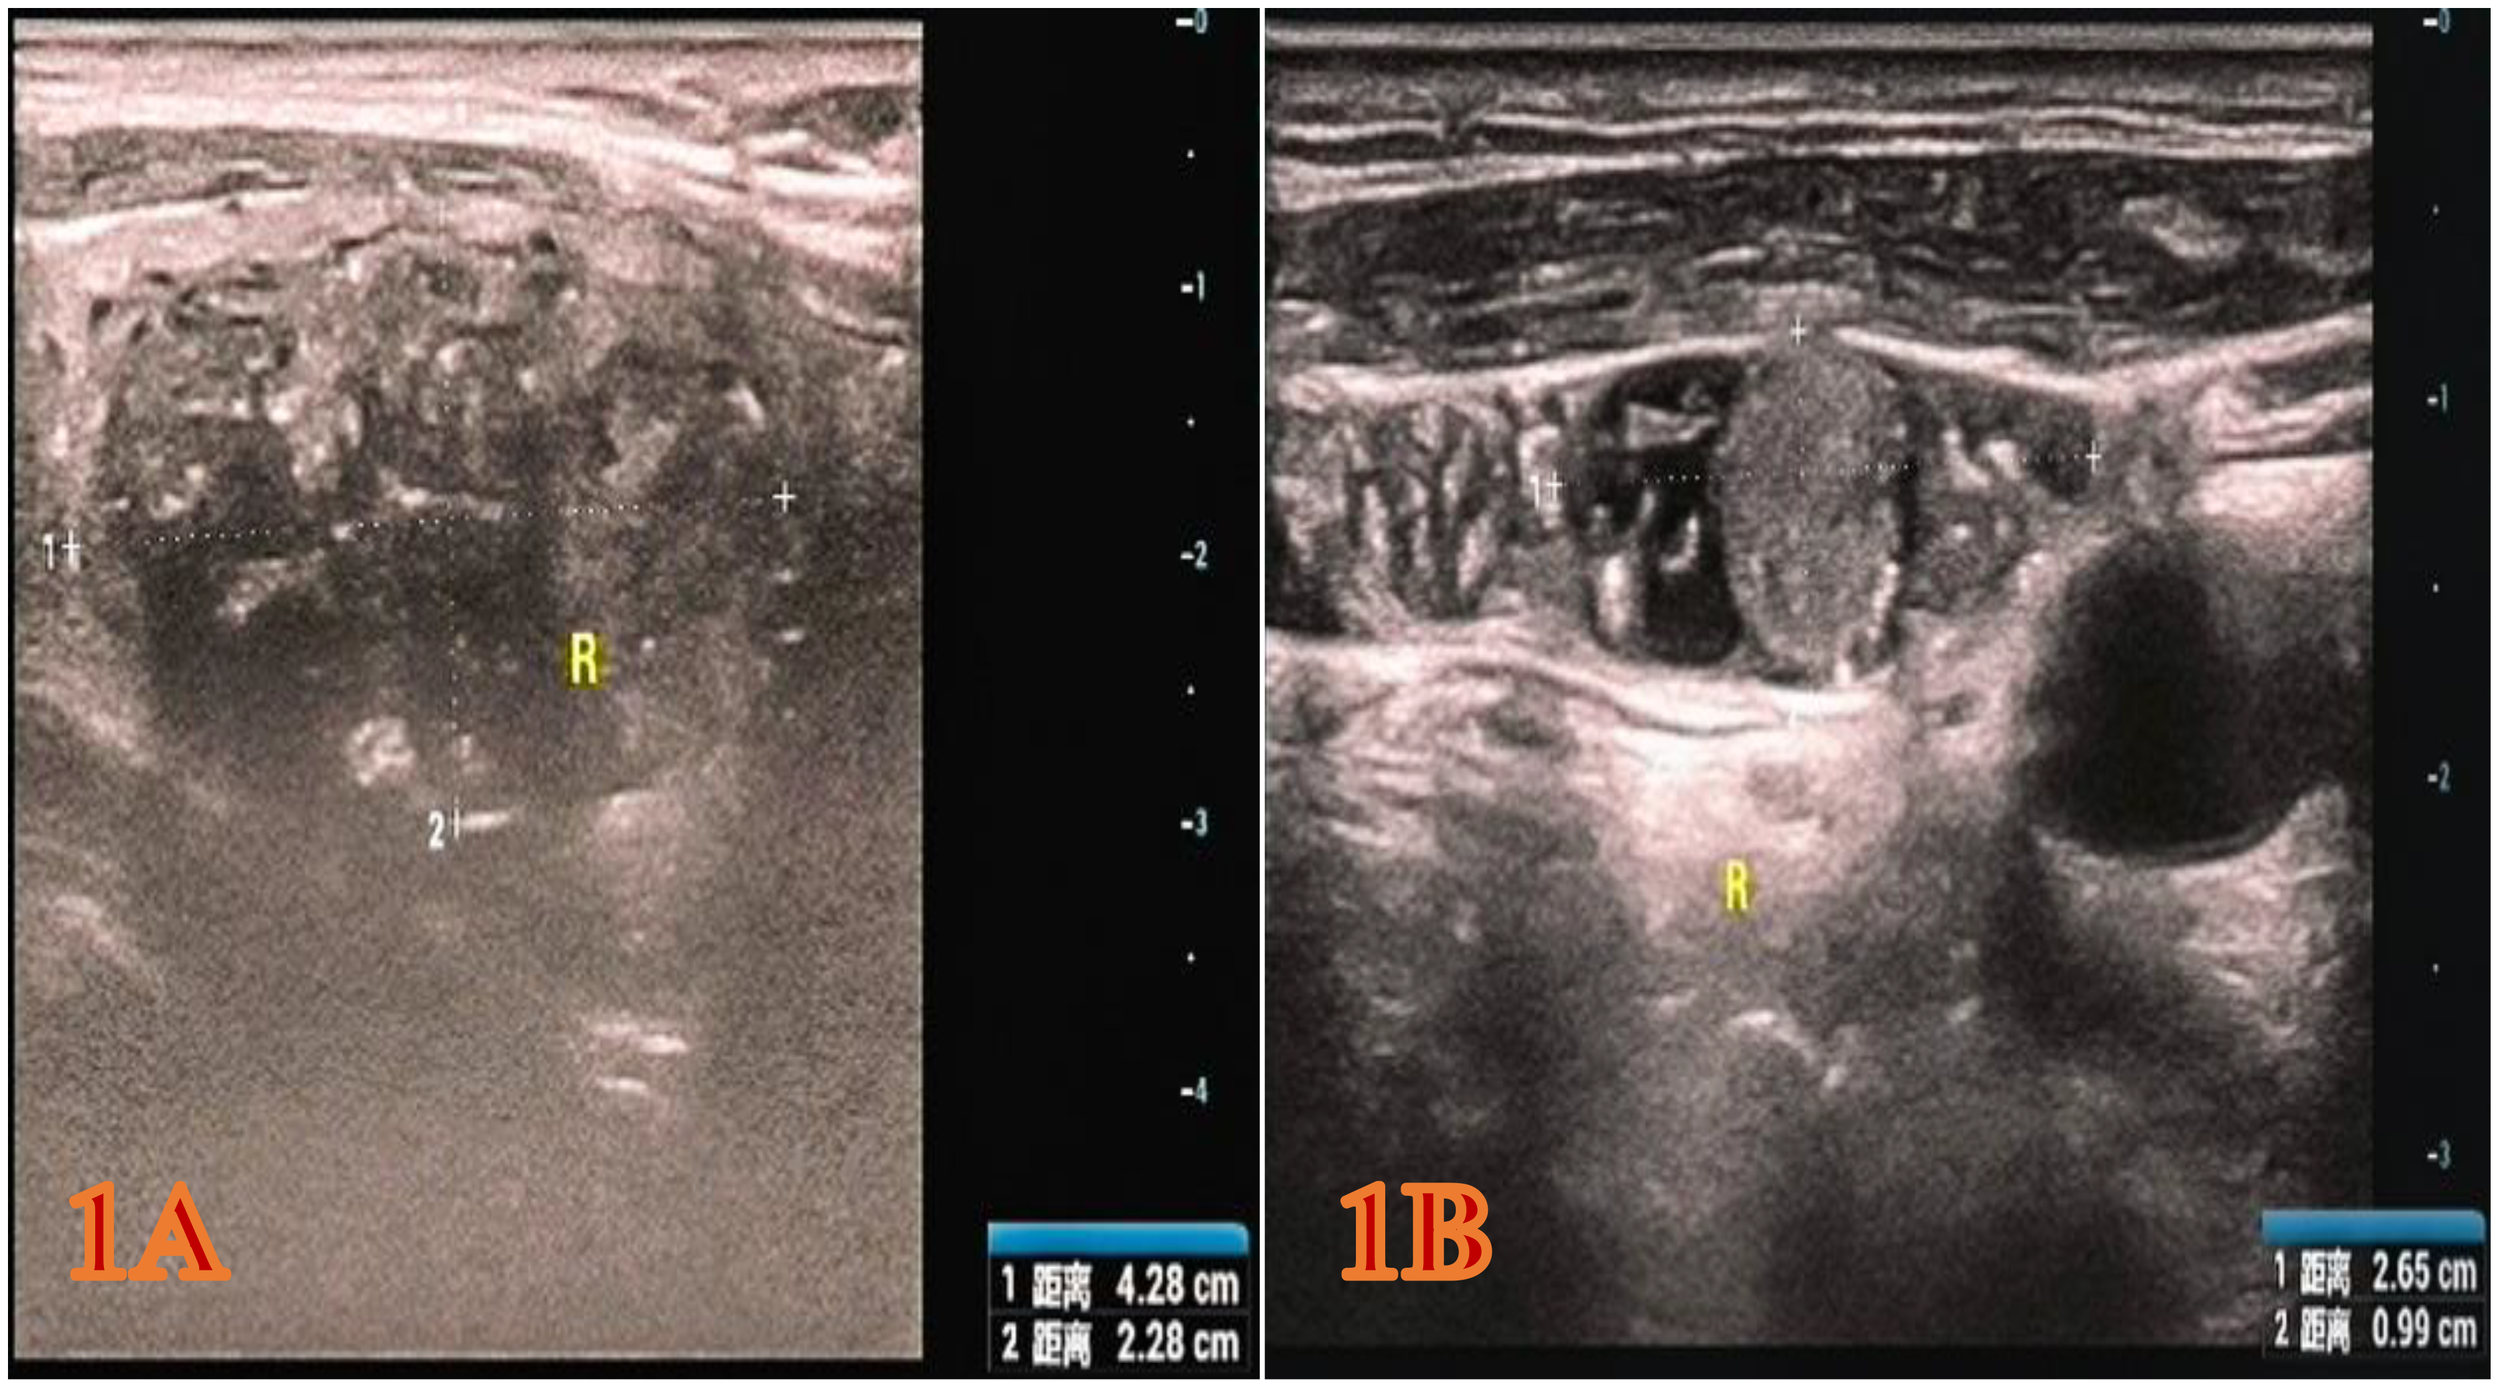

The patient is a 65-year-old Han male. During a physical examination at Mianyang Third People’s Hospital, a color Doppler ultrasound of the thyroid gland was performed, which revealed a hypoechoic nodule in the right lobe of the thyroid gland, measuring 4.28x2.28x2.54 cm (Figure 1A). The shape was relatively regular, with some unclear boundaries. Within it, scattered punctate and mass-like hyperechoic areas of varying sizes were observed. The TI-RADS classification was 5. A cystic nodule was also found in the left lobe of the thyroid gland, classified as TI-RADS 2. Color Doppler ultrasound of bilateral cervical and supraclavicular lymph nodes suggests an enlarged lymph node on the right side of the neck (the largest one measures 2.65x0.99 cm) with structural abnormalities (Figure 1B). The patient was subsequently admitted to the thyroid and maxillofacial surgery department for treatment. The patient has no history of tumors or family history of tumors in the past. Physical examination revealed a hard mass about 4.0 cm in diameter in the right lobe of the thyroid gland, with moderate mobility and no obvious tenderness. No obvious nodules were palpable in the left lobe of the thyroid gland, and no enlarged lymph nodes were palpable in the bilateral neck. Laboratory test results show that serum CT level is 1796.38 pg/ml, CEA is 81.69 ng/ml, and TG is 163.65 ng/ml. All these indicators are above the normal range. The results of thyroid function tests are normal.

Figure 1

The color Doppler ultrasound image of the patient during the physical examination. (A) Right thyroid gland (hypoechoic nodule, 4.28x2.28x2.54 cm, heterogeneous hypoechoic, TI-RADS category 5). (B) Right cervical lymph nodes (the larger one approximately 2.65 x 0.99 cm, considered enlarged lymph nodes with structural abnormalities).